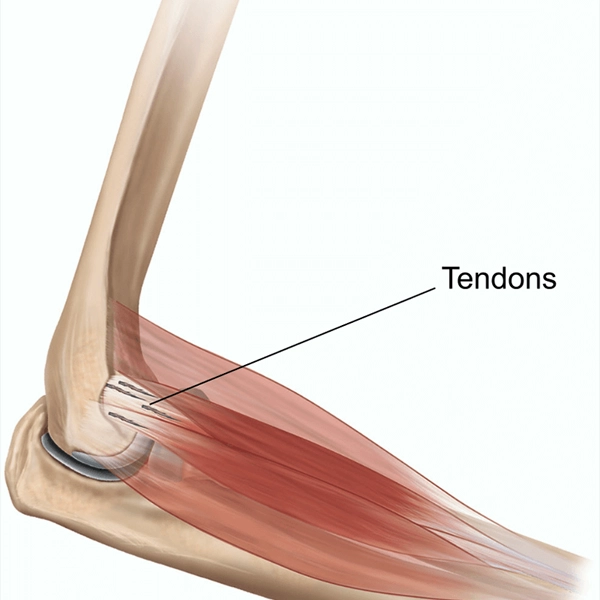

تاندون آرنج چرا آسیب میبیند؟

تاندون آرنج معمولاً بهدلیل فشارهای مکرر و بیشازحد در تمرینات ورزشی آسیب میبیند. وقتی ورزشکار حرکات را با تکنیک نادرست انجام میدهد یا بدون گرم کردن کافی تمرین میکند، این فشار روی تاندون افزایش مییابد. همچنین انجام حرکات تکراری بدون استراحت مناسب باعث خستگی و ضعف تاندون میشود که زمینه پارگی را فراهم میکند. بهطور خلاصه، عدم رعایت اصول تمرینی و استراحت کافی مهمترین عوامل آسیبدیدگی تاندون آرنج هستند.